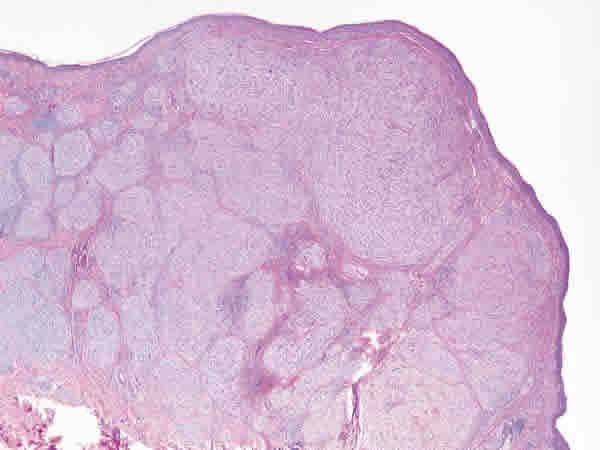

Fig. 1: Tumoración dérmica con patrón de crecimiento plexiforme.